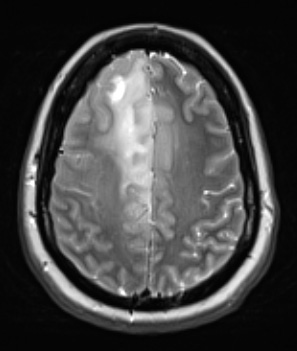

Case 8 History ---- The patient is a 45-year-old woman with a history of hypertension and increasing headaches since November 2016. MRI showed T2 vascular hyperintense lesions in the right frontal lobe and meningeal left frontal lobe white matter, favoring a glial neoplasm versus lymphoma. Operative procedure: Right frontal craniotomy for biopsy of brain tumor. ---- 8A1 The lesion is represented by a diffuse hyperintensity of the right frontal lobe in this T2-weighted contrast administered scan.